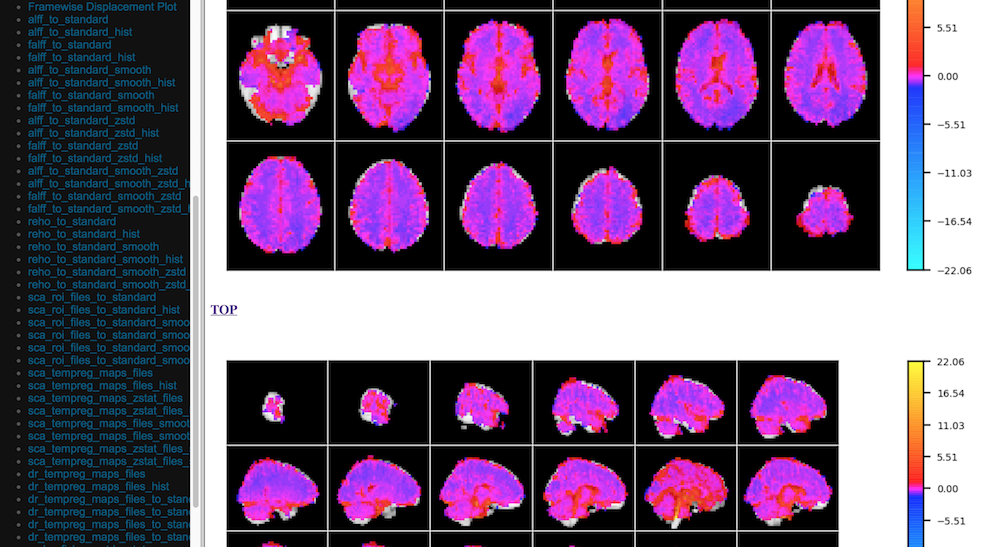

Visual Quality Control

C-PAC’s data quality control (QC) interface allows you to take a quick glance at the overall quality of your results (registration quality, signal-to-noise ratio, movement plots, computed derivative histograms, etc.). In its current form, the QC interface is a collection of HTML pages - one for each participant-scan-nuisance regression strategy combination, and they can be found in the Output Directory under each participant’s directory level.

Quick View of Derivatives

../_images/qc_interface3.png

With Histograms

../_images/qc_interface4.png